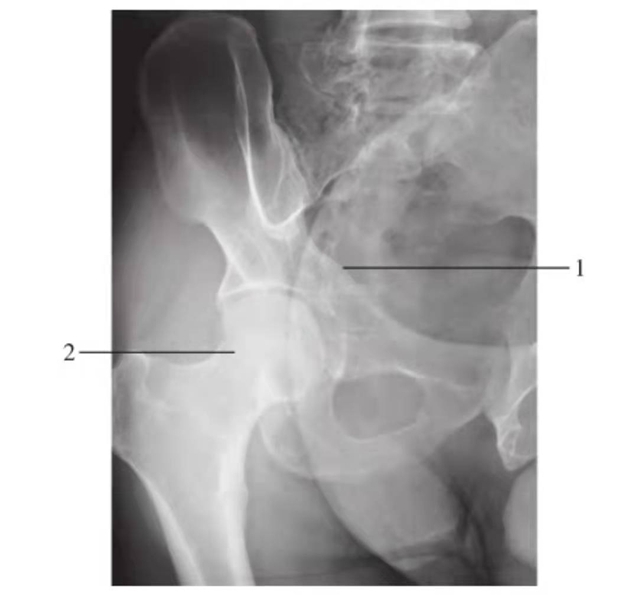

闭孔斜位

图9 右侧闭孔斜位

1.前柱;2.髋臼后唇